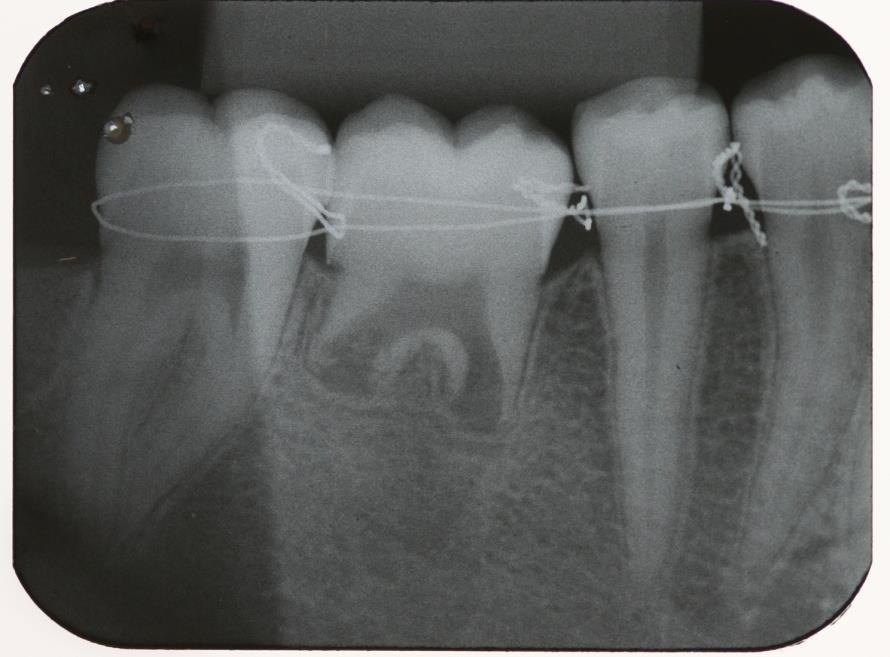

Após sutura do tecido foi feito contenção semi-rígida com fio ortodôntico n° 0 para fixação do elemento dentário no alvéolo, posicionado elemento transplantado abaixo da linha de oclusão para evitar traumas oclusais (figura 8 e 9).

Longo prazo de proservação avaliando imagens radiográficas bem como exames clínicos, retirada da contenção após 60 dias, só então afirmar sucesso no procedimento cirúrgico realizado. (figura 10 e 11).